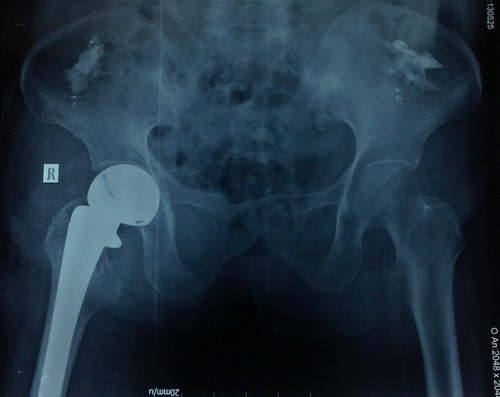

| Hình ảnh phim chụp khớp háng bệnh nhân 93 tuổi. Ảnh: T. Đ.P |

Bác sĩ Phú cho biết, bệnh nhân được nhanh chóng phẫu thuật thay khớp háng chuôi dài thế hệ mới. Đây là loại khớp háng mới được ứng dụng cho các loại gãy cổ xương đùi phức tạp có đường gãy lan xuống dưới làm mất vững. Sau hậu phẫu 7 ngày, bệnh nhân đã vận động nhẹ tại giường chân phải và bớt đau đớn. Khả năng sau 3 ngày nữa là bệnh nhân có thể xuất viện.